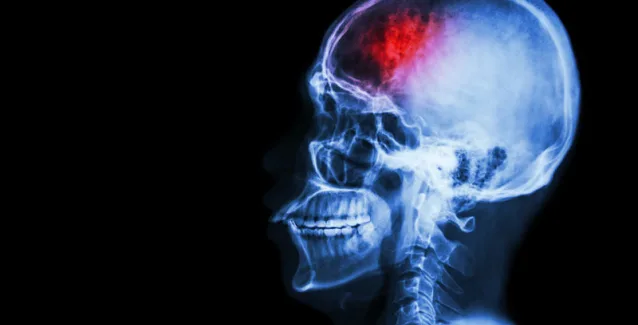

Η διατροφή μπορεί να παίξει σημαντικό ρόλο στην εξέλιξη της υγείας του ανθρώπου και σύμφωνα με έρευνα, οι καλές πρωτεΐνες μειώνουν τον κίνδυνο εγκεφαλικού επεισοδίου.

Ερευνητές της Ιατρικής Σχολής του Πανεπιστημίου του Ναντζίνγκ, στην Κίνα, αξιολόγησαν επτά έρευνες για τη σχέση πρωτεϊνών και εγκεφαλικού επεισοδίου, οι οποίες αφορούσαν 255.000 άτομα από τις ΗΠΑ, την Ιαπωνία, και τη Σουηδία, για μια περίοδο τουλάχιστον δέκα ετών.

Από την επεξεργασία των δεδομένων διαπιστώθηκε ότι, όσοι περιλάμβαναν πολλές πρωτεΐνες στη διατροφική τους καθημερινότητα, τρώγοντας κυρίως ψάρια και όχι κόκκινο κρέας, είχαν 20% μικρότερο κίνδυνο να υποστούν εγκεφαλικό επεισόδιο, συγκριτικά με εκείνους που δεν περιλάμβαναν επαρκείς ποσότητες πρωτεϊνώνστο διαιτολόγιο τους.

Μάλιστα, η μείωση του κινδύνου είναι μεγαλύτερη, όταν οι επιπλέον πρωτεΐνες είναι ζωικής προέλευσης, συγκριτικά με τη μείωση που επιτυγχάνεται με τις φυτικές πρωτεΐνες. Βέβαια, θα πρέπει να επισημανθεί ότι οι ζωικές πρωτεΐνες δεν πρέπει να ταυτίζονται πάντα με κρέας, αφού η αυξημένη κατανάλωση κόκκινου κρέατος οδηγεί σε αύξηση του κινδύνου για εγκεφαλικό επεισόδιο.

Η ποσότητα της πρωτεΐνης που χρειάζεται να καταναλώνει κανείς καθημερινά για να έχει μειωμένο κίνδυνο εγκεφαλικού επεισοδίου, καθορίστηκε στα περίπου 20 γραμμάρια. Για κάθε 20 πρόσθετα γραμμάρια πρωτεϊνών που καταναλώνει κανείς ημερησίως, ο κίνδυνος μειώνεται κατά 26%.

Η μείωση του κινδύνου εξακολουθούσε να ισχύει ακόμη και όταν οι επιστήμονες συνεκτίμησαν παράγοντες όπως, η υπερχοληστερολαιμία, ή το κάπνισμα.

Οι πρωτεΐνες μειώνουν την αρτηριακή πίεση και αυτό πιθανώς εξηγεί εν μέρει την προστατευτική δράση τους στην περίπτωση του εγκεφαλικού επεισοδίου.